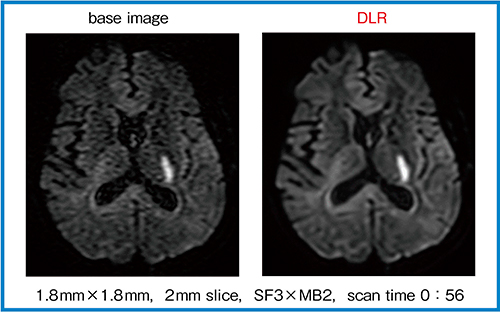

DLRの特長として,さまざまなシーケンスに適用可能なことが挙げられる。特に,ノイズの多い画像に有用なことから,拡散強調画像(DWI)には大きな効果が期待できる。図3は実際の画像であるが,DLR処理後はノイズが除去されて非常に見やすく,解剖学的なコントラストも明瞭になっている。また,ここから作成した拡散テンソル画像(DTI)のカラーマップ(図4)も,DLR処理によって末梢のノイズが除去され,髄枝も明瞭に描出されている。

図3 DWI(b=1000,1direction)におけるDLRの効果(W.I.P.)